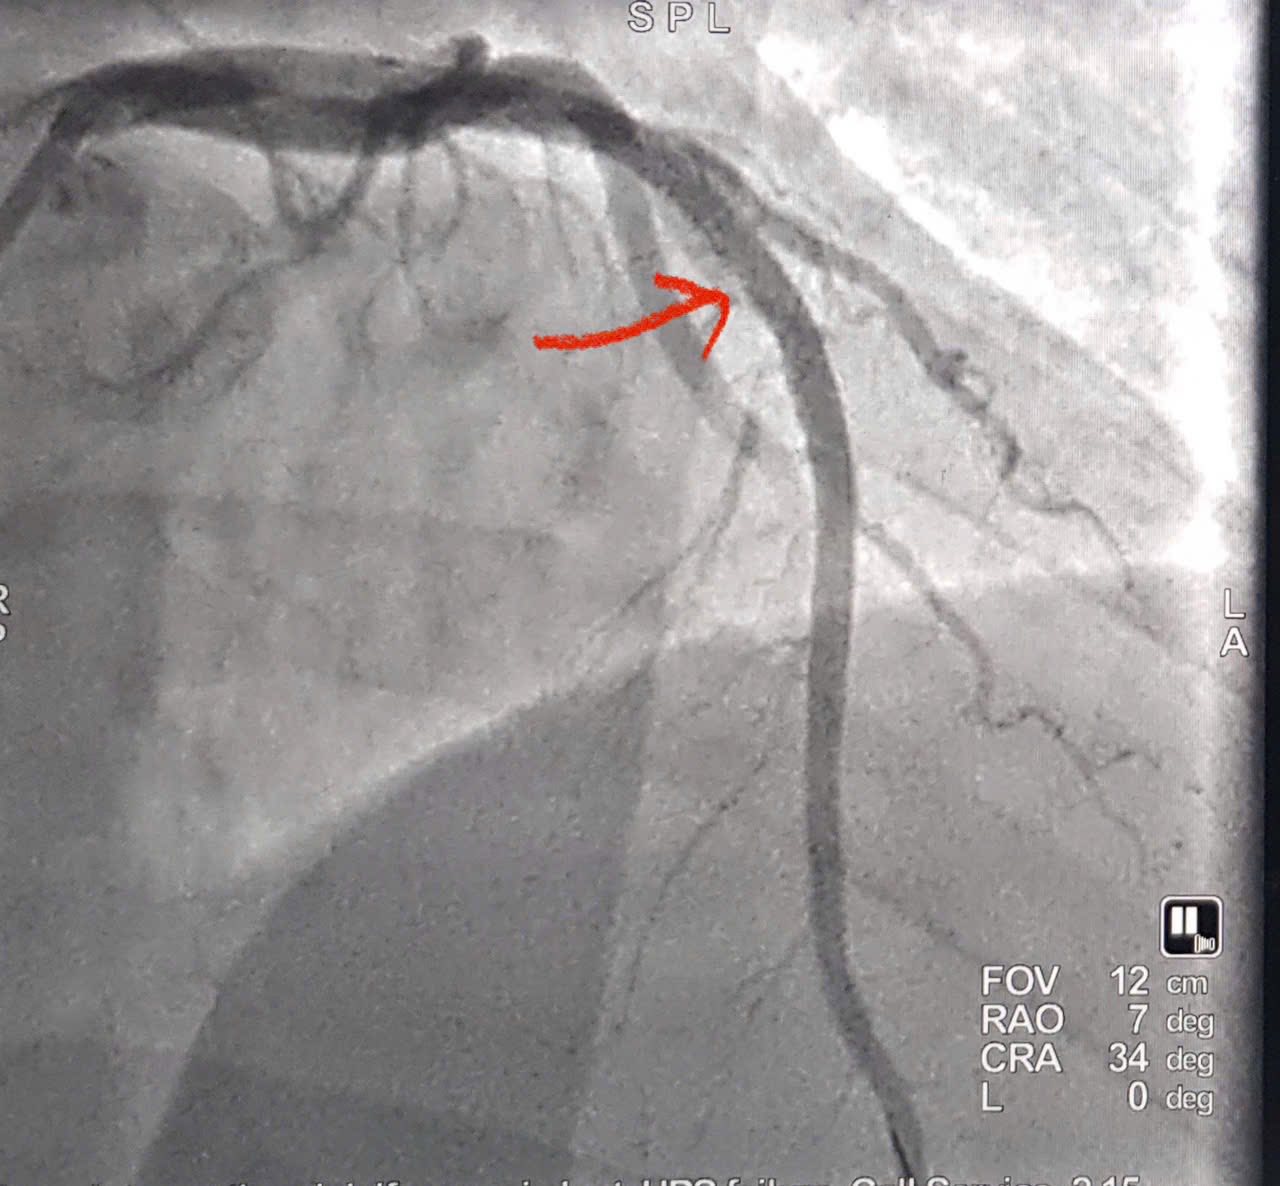

Hình ảnh động mạch vành được tái thông |

Bệnh nhân được chỉ định chụp động mạch vành cấp cứu bằng hệ thống chụp mạch số hóa xóa nền (DSA) qua đường động mạch quay phải – phương pháp hiện đại, ít xâm lấn, giúp rút ngắn thời gian can thiệp và giảm biến chứng.

Kết quả chụp mạch cho thấy tắc hoàn toàn động mạch liên thất trước đoạn II (LAD II) – nhánh mạch vành quan trọng cung cấp máu cho phần lớn cơ tim thất trái. Ê-kíp can thiệp đã nhanh chóng tiến hành nong bóng và đặt một stent phủ thuốc tại vị trí tổn thương (Theo hình ảnh minh hoạ). Thủ thuật diễn ra thuận lợi, dòng máu được tái lập ngay sau can thiệp, cải thiện rõ rệt tình trạng thiếu máu cơ tim. Trong cấp cứu nhồi máu cơ tim, yếu tố quyết định là thời gian. Mỗi phút trôi qua là một phần cơ tim bị hoại tử. Việc tái thông mạch vành càng sớm thì khả năng bảo tồn chức năng tim càng cao.